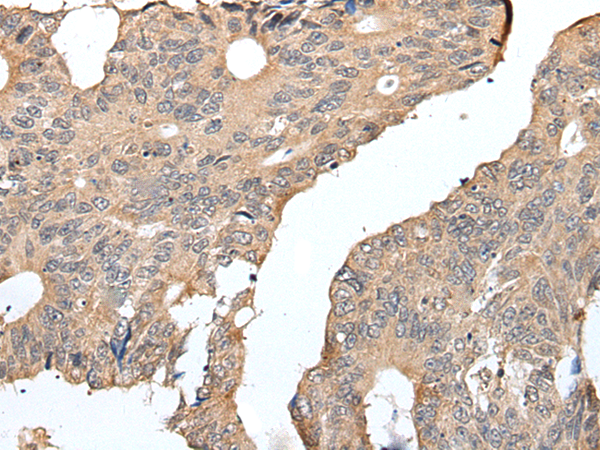

IHC positive control: |

Human colorectal cancer |

IHC Recommend dilution: |

25-100 |